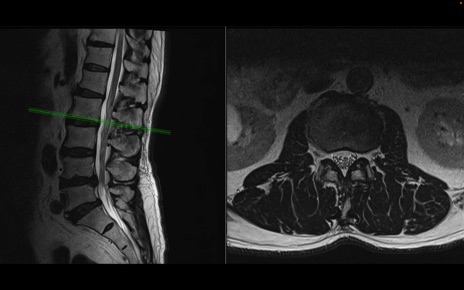

【整形】TIPS症例2 腰椎MRI 横断像と矢状断像

【症例】70歳代男性

【主訴】左下肢痛

【現病歴】2週間前くらいから腰痛、左下肢痛あり。左臀部から大腿、下腿外側のしびれが常時ある。歩行とともに同部位の痛みあり。

【身体所見】Lasegue70-/60+、Bragard-/±、PTR ±/±、ATR -/-、IP 5/5、TA 5/4、TS 5/5、EHL 右第1足趾なし/3、FHL 5/5、hypersthesia(-)、足背動脈触知良好

異常所見と診断は?